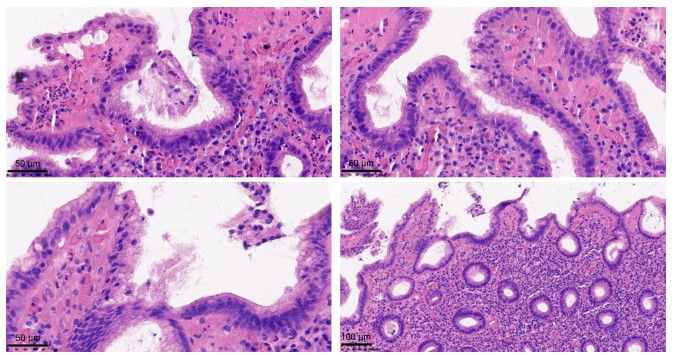

Study on the relationship between the nature of cold and heat of IBS-D and changes in gut microbiota and metabolites

TANG Binbin, HU Yunlian, SU Chengxia, HUANG Chaoqun, WEN Na

2025, 23(10): 1658-1662. doi: 10.16766/j.cnki.issn.1674-4152.004199

63 3

Abstract:

Objective  To investigate the correlation between changes in gut microbiota and metabolites and the nature of cold and heat in traditional Chinese medicine (TCM) through diarrhea-predominant irritable bowel syndrome (IBS-D) rat models with cold-dampness syndrome and damp-heat syndrome.  Methods  Thirty newborn rats were divided into a healthy group, a damp-heat group, and a cold-dampness group using the random number table method, with 10 rats in each group. The damp-heat group was subjected to maternal separation, restraint stress, a high-fat and high-sugar diet, and a damp-heat environment to establish an IBS-D rat model with damp-heat syndrome. The cold-dampness group was subjected to maternal separation, restraint stress, and intragastric administration of senna leaves to establish an IBS-D rat model with cold-dampness syndrome. Subsequently, 16S rRNA sequencing and non-targeted metabolomics were employed to detect the gut microbiota and fecal metabolites of the rats in each group, respectively, followed by bioinformatics analysis.  Results  Significant differences in β-diversity were observed among the rat groups (P=0.001). Specifically, bacterial genera such as Clostridium_sensu_stricto_1, Roseburia, and Prevotella were enriched in the damp-heat group, whereas Dubosiella, Akkermansia, and Romboutsia were enriched in the cold-dampness group. The disrupted metabolic pathways in the damp-heat group rats primarily involved alanine, aspartate, and glutamate metabolism. In contrast, the cold-dampness group rats exhibited disruptions in steroid hormone biosynthesis, tryptophan metabolism, and histidine metabolism. The differential pathways between the damp-heat and cold-dampness groups mainly involved pantothenate and CoA biosynthesis, histidine metabolism, and glycerophospholipid metabolism.  Conclusion  There are differences in the characteristics of gut microbiota and metabolites between IBS-D with cold-dampness syndrome and damp-heat syndrome. The changes in gut microbiota and metabolites might be the microscopic manifestations of the nature of cold and heat in TCM.